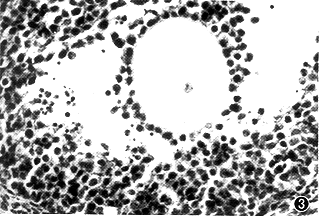

以正常兔IgG作为免疫原的小鼠卵巢组织中存在各个阶段发育卵泡,多数无形态学改变。Ab2免疫组早期生长卵泡形态正常,晚期生长卵泡出现核固缩及凋亡小体,颗粒细胞出现“脱屑”现象,细胞核固缩(图1,2)。17D3mAb-ZP免疫组,形态上同Ab2组,但颗粒细胞损伤程度较Ab2组重,并出现闭锁卵泡(图3);PZP免疫组各阶段发育卵泡数量明显减少,大量颗粒细胞损伤,出现核固缩,核碎片及凋亡小体,卵巢间质黄素化(图4)。

图3 17D3mAb靶抗原免疫小鼠的卵巢组织形态学